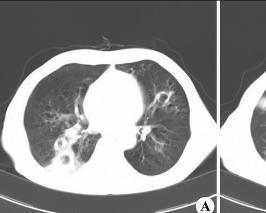

肺脓肿是由于多种病因所引起的肺组织化脓性病变。早期为化脓性炎症,继而坏死形成脓肿。多发生于壮年,男多于女。根据发病原因有经气管感染型、血源性感染型和多发脓肿及肺癌等堵塞所致的感染型3种。肺脓肿也可以根据相关的病原进行归类,如葡萄球菌性、厌氧菌性或曲霉菌性肺脓肿。自抗生素广泛应用以来,肺脓肿的发生率已大为减少。